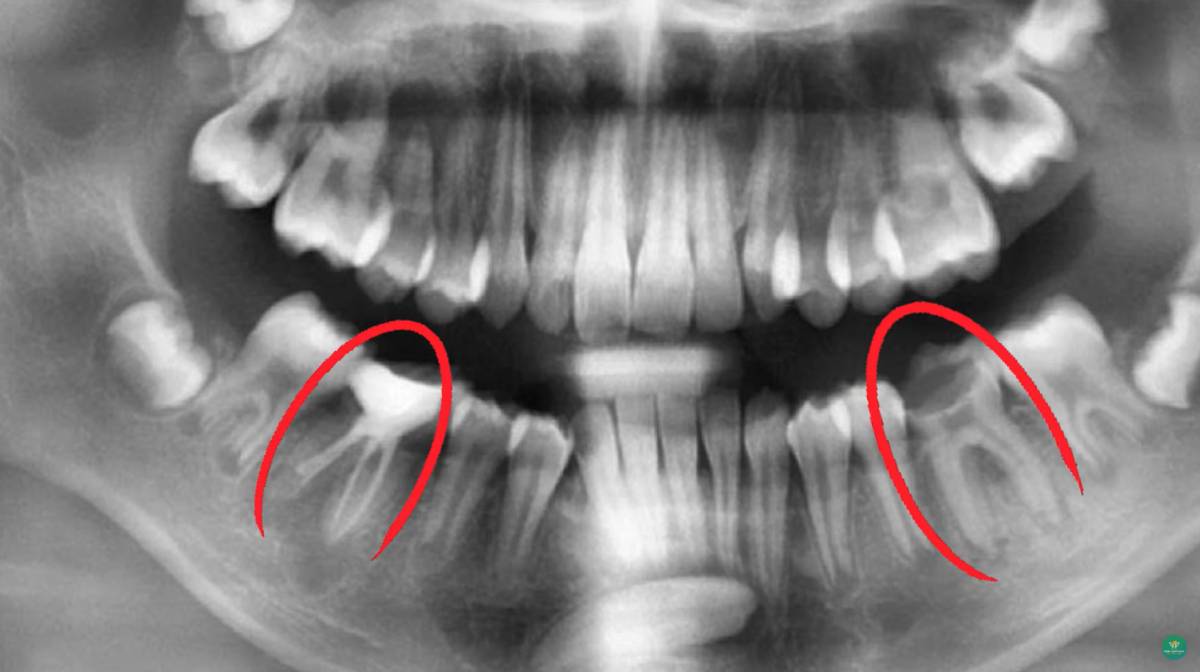

Để xác định chính xác tình trạng răng mọc ngầm, bác sĩ sẽ chỉ định chụp X-quang toàn hàm hoặc CT Cone Beam. Nhờ đó, có thể đánh giá được vị trí, chiều hướng mọc, mức độ ảnh hưởng đến răng và xương xung quanh.

Việc chẩn đoán sớm giúp lên kế hoạch điều trị kịp thời, giảm nguy cơ biến chứng và bảo vệ răng vĩnh viễn.